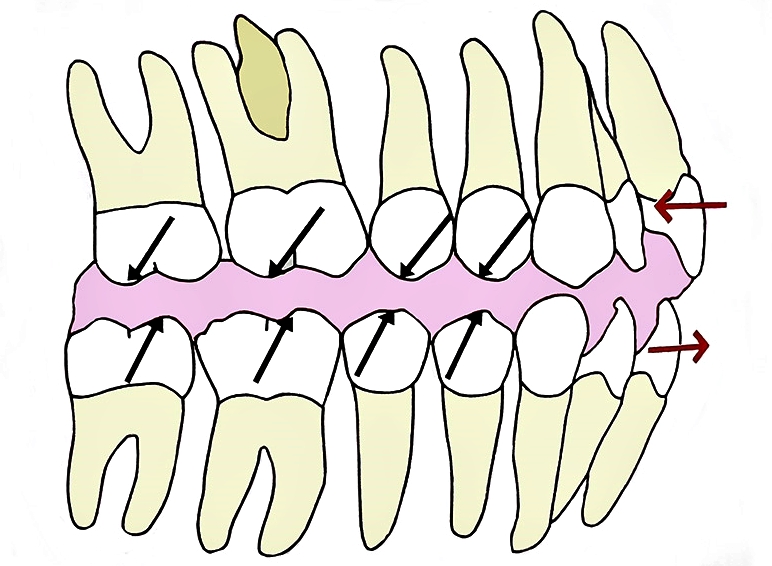

예전 포스팅에서 어린이 무턱 교정 치료에 관하여 설명드린 적이 있습니다. 무턱은 위턱의 성장이 많거나 아래턱 성장이 덜 되어 악골간의 성장 부조화가 있을 경우 발생하게 됩니다. 따라서 과성장된 상악을 헤드기어로 억제하며 상대적으로 발달이 덜 된 하악을 2급 액티베이터(Class II activator)를 사용하여 성장을 유도하게 됩니다.

액티베이터의 작용기전